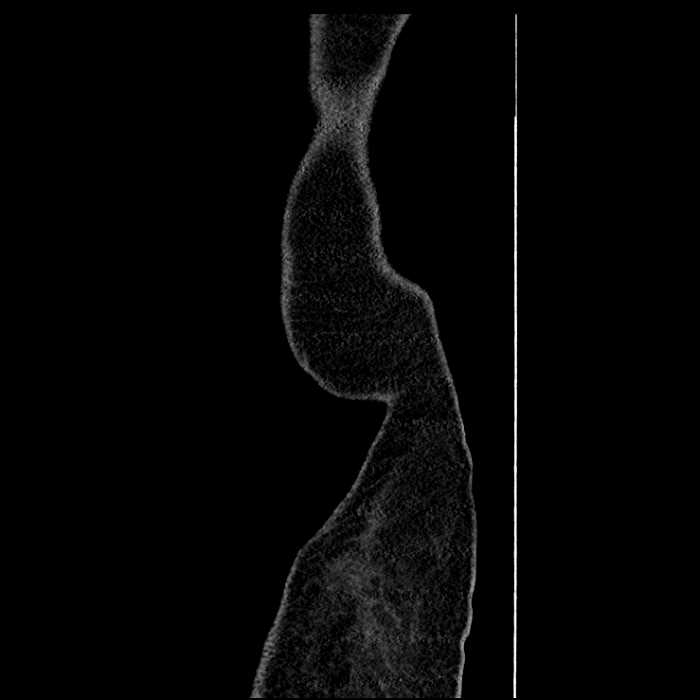

• Mild mural thickening of a segment of the sigmoid colon with adjacent fat stranding and a 1.5 cm fluid and gas collection along the tip of an inflamed diverticulum

• Loss of the normal fat plane between this collection and adjacent loops of small bowel, which demonstrate mural thickening

Acute sigmoid diverticulitis complicated by a small contained perforation and a large abscess in the right hepatic lobe. Additional small subcapsular abscesses along the anterior margin of the left hepatic lobe.

Additionally, loss of the normal fat plane between the peridiverticular collection and adjacent thickened loops of small bowel raises the potential for an enterocolonic fistula.

Hepatic abscess showing the double target sign with low density internally surrounded by a thin inner enhancing rim (red arrow) and ill-defined outer low density rim (yellow arrow). Blue arrow indicates an internal septation. Red arrows: additional smaller subcapsular abscesses. Red arrow: focal contained perforation associated with diverticulitis.